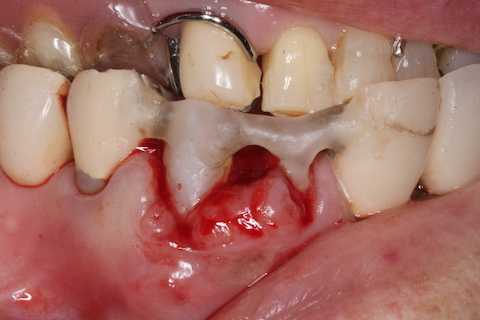

前回 ​のつづきで、再植と化粧をする。さすがに歯なしでは寂しい。

普通にズブズブと抜歯窩に再建した歯根を挿入する。